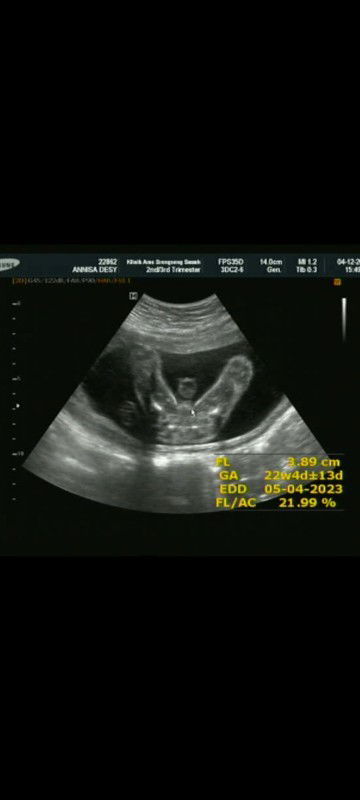

Bun mau tanya, saya kan tgl 24 November kemarin kontrol ulang di puskesmas dan disuruh Dateng lagi tgl 25 Desember, terus tgl 5 Desember saya ke klinik untuk USG saja tapi dari klinik nya disuruh Dateng lagi tgl 6 Januari, saya bingung Bun mau Dateng kontrol ulang di puskesmas apa di klinik ya? #seriusnanya #bantusharing #firstmom #firstbaby